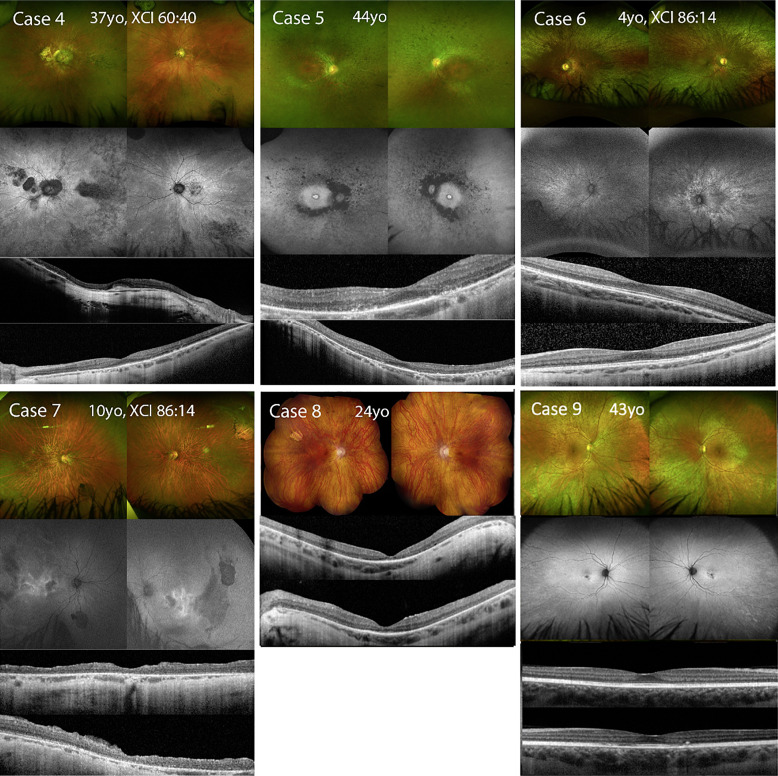

Case presentations: Three affected simplex CHM carriers and six affected simplex XLRP or XLCORD carriers due to variants in RPGR (n = 5) or RP2 (n = 1) were included. Best corrected visual acuity, color fundus photos, fundus autofluorescence (FAF), optical coherence tomography, electroretinography, and Goldmann visual fields were collected. X-chromosome inactivation (XCI) ratios were determined for 4 cases. Age of onset ranged from infancy to 43 years, with nyctalopia as the most common presenting symptom. 4 out of 5 cases with RPGR variants presented with cone or cone-rod dystrophies, while the remaining cases presented with rod-cone dystrophy. XCI analysis revealed extreme skewing in 2 cases who both presented with severe disease. 4 out of 7 cases with FAF demonstrated autofluorescence patterns classic for carrier status. The remaining 3 cases had severe disease and corresponding FAF patterns consistent with their severity.